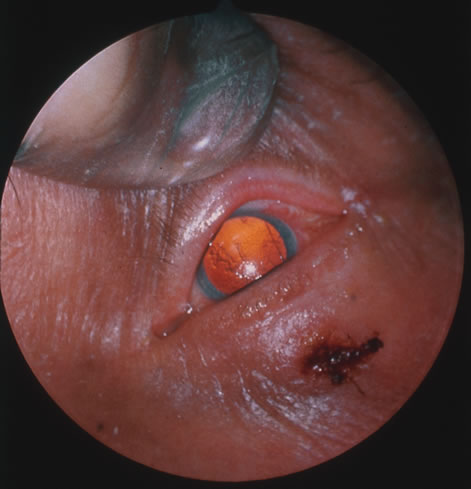

Penicillin G is the drug of choice for syphilis. Primary or secondary syphilis of less than 1 year's duration may be treated with a one-time intramuscular injection. The CDC recommends treatment of syphilis of longer than 1 year's duration with penicillin G, 2.4 million units intramuscularly weekly for 3 weeks. Neurosyphilis requires treatment with intravenous penicillin every 4 hours for 10 to 14 days as does congenital syphilis. Oral doxycyline or tetracycline has been recommended for those with a documented penicillin allergy.76 LEPTOSPIROSIS Leptospirosis is a waterborne disease common to tropical climates that is caused by the spirochete Leptospira interrogans. Wild animals and rodents are considered reservoirs of this disease. Animals are infected via water or soil that is contaminated with the spirochete. Humans in turn acquire disease through contact with animal urine or infected animal tissue.77 The first phase of the illness is characterized by frontal or retro-orbital headache, severe myalgia, and high fever. Leptospira organisms are present in the blood and cerebrospinal fluid during this period, which lasts 4 to 9 days. Defervescence and a decrease in symptoms occur over the next few days. A second (immune) phase follows, with return of fever and symptoms. Ocular involvement occurs during the second, or immune, phase of the disease. Conjunctival injection and subconjunctival hemorrhages may be present. Unilateral or bilateral uveitis, occasionally with hypopyon, has been reported with leptospirosis.78 The prognosis for this uveitis is generally good. About 90% of patients develop relatively mild systemic disease. Less commonly, patients develop jaundice, hepatomegaly, and hemolytic anemia that occasionally results in death. Overall mortality is 5% to 7%. Patients older than 50 years are at much greater risk of fatal disease. The gold standard for diagnosis of leptospirosis is the serologic microagglutination test. This test determines a rise in antibody titer that is considered diagnostic of infection. Treatment of systemic leptospirosis is with penicillin or tetracycline. RELAPSING FEVER Relapsing fever is a syndrome of cyclic febrile and afebrile intervals, caused by various species of the spirochete Borrelia. The two major types of relapsing fever are named by their vectors, lice and ticks. Louse-borne relapsing fever is caused by B. recurrentis, transmitted by the human body louse.79 It is endemic to parts of Africa, South America, and the Far East and occurs as epidemics in wartime and famine. Tick-borne relapsing fever is caused by many species of Borrelia and occurs mainly in the western mountain states in the United States but has also been reported in Africa, Europe, Asia, and South America. It is transmitted by the bite of a soft-bodied tick belonging to the genus Ornithodoros. Spirochetemia produces an abrupt onset of headache, fever, rigors, nausea, myalgia, and arthralgia. Petechiae, epistaxis, and microscopic hematuria occur frequently, and more severe bleeding manifestations may be seen. Hepatosplenomegaly is common. Arrhythmias, heart failure, jaundice, and neurologic signs may be features. Several days after onset, a chill and an abrupt rise in temperature and in blood pressure, heart, and respiratory rates occur, described as a “crisis.” The organisms are then cleared from the bloodstream by immobilizing antibodies, and the patient becomes diaphoretic and hypotensive. Cardiovascular collapse may occur at this time, but usually blood pressure and temperature normalize and the patient becomes comfortable. About 1 week later, relapse occurs with similar findings. Louse-borne fever tends to be more severe and relapse only once, whereas tick-borne fever is a milder disease with more numerous cycles. Ocular manifestations have only been reported during tick-borne relapsing fever. Ocular involvement usually occurred only after several cycles of febrile episodes and led to rapidly devastating visual loss. Iritis is the most common ocular manifestation. Optic neuritis, choroiditis, retinal venous congestion, hemorrhage, and exudate have been reported. Cranial nerve palsies may cause motility disturbances or ptosis.80 Diagnosis is made by demonstrating organisms on Giemsa or Wright's-stained blood smears during the febrile phase. Phase-contrast microscopy of wet mounts may be helpful. Blood specimens may also be injected into laboratory animals and their blood subsequently examined for spirochetemia. Anemia and thrombocytopenia are common. Leukopenia occurs during the crisis. Tetracycline and long-acting penicillins have been recommended as treatment for tick-borne and louse-borne disease, respectively. A single intramuscular injection of penicillin is effective in treatment of louse-borne disease.81 Tick-borne disease, on the other hand, requires treatment for several days and tetracycline appears to be the drug of choice. It is most effective when administered during the first febrile episode, and it is continued for 5 to 10 days. Mortality rates may be significant in epidemics of louse-borne disease. RICKETTSIOSIS Rickettsiae are gram-negative coccobacilli borne by insect vectors and causing disease characterized by fever, headache, and rash. In the United States, Rocky Mountain spotted fever is the most commonly reported rickettsial disease. While rickettsiae are transmitted by ticks, mites, fleas, and lice, it is the bite of the tick Dermacentor (imlils) variabilis and D. andersoni that transmits Rickettsia rickettsii, which is responsible for Rocky Mountain spotted fever. The states most commonly cited as having the highest incidence of reported cases are the Carolinas, Oklahoma, and Tennessee, however, an outbreak was reported in New York City in 1988.82 Reports vary from 600 to 1200 cases annually and peak in the spring and summer months. The classic triad of symptoms includes fever, rash, and exposure to a tick bite. The exanthem that begins approximately 1 week after exposure is the most characteristic sign of the disease, although it may not develop in up to 10% of confirmed cases.83 A macular rash appears around the wrists and ankles eventually spreading to involve the trunk, face, palms, and soles. Delay in diagnosis and treatment may result in a widespread vasculitis resulting in death from disseminated intravascular coagulation. Ocular signs of rickettsiosis include conjunctivitis varying from mild to granulomatous and ulcerative, conjunctival petechiae, keratitis, anterior and posterior uveitis, vitreous opacities, retinal venous engorgement, arteriolar and venous occlusions, cotton-wool spots, retinal hemorrhage and exudates, perivasculitis, and optic nerve head and retinal edema. Other than symptomatology, diagnosis is made using serology. Antibodies may be detected 7 to 10 days after onset of illness. The Weil-Felix assay involves agglutination to various strains of Proteus vulgaris and is a nonspecific test that is no longer recommended. Although rarely used, the PCR technique to detect R. ricketsii antigen and direct immunofluorescent testing of skin biopsies is available.84 Antibiotic treatment of choice is tetracycline for 5 to 7 days or 48 hours after resolution of fever. Oral chloramphenicol is substituted in children and intravenous chloramphenicol is preferred in patients with central nervous system disease. CAT-SCRATCH DISEASE Cat-scratch disease is an infectious disorder caused by a small gram-negative bacterium classified in the early 1990s as Bartonella henselae.85 The disease is commonly transmitted by the scratch of a domestic cat. Patients frequently develop flu-like symptoms and regional lymphadenopathy in the nodes that drain the inoculation site. Cat-scratch disease occurs throughout the United States and the world. The incidence of cases is greatest in the second half of the year. The organism that causes cat-scratch disease can enter the body through the conjunctiva or any break in the skin, including an insect bite, abrasion, or puncture wound. A probable inoculation site can be found in 92% of patients. It first appears as a pink or red papule that, over the next 3 days, successively becomes vesicular, pustular, and finally a crusted lesion. A remaining macule may be observed for as long as 2 to 3 months. Within 1 or 2 weeks of exposure, lymphadenopathy develops. Because most contact with cats is with the hands and arms, axillary and epitrochlear adenopathy is the most common. This is followed in decreasing prevalence by cervical, submandibular, inguinal, preauricular, femoral, clavicular, and postauricular involvement. Suppuration occurs in approximately 11% to 48% of cases. Patients also generally experience body aches, fever, malaise, anorexia, and rarely nausea and abdominal pain. In a small percentage of cases inoculation occurs through the conjunctiva and results in a granulomatous conjunctivitis and preauricular adenopathy (Parinaud's syndrome). The inoculation site can at times be recognized as an area of soft granulation tissue that causes little erythema of the surrounding tissue. Other uncommon manifestations include encephalitis (1% to 2%), osteomyelitis (less than 1%), and erythema nodosum. Ocular involvement occurs in fewer than 10% of patients with cat-scratch disease (Fig. 22).86 In addition to Parinaud's oculoglandular syndrome, other manifestations include neuroretinitis, focal or mutilfocal retinochoroiditis, branch retinal artery and vein occlusions, serous macular detachments and optic disc edema associated with peripapillary serous retinal detachments.87 B. henselae is thought to be the most common cause of neuroretintis, which is characterized by optic disc edema and a macular exudates in the form of a star.88 Other possible etiologies of neuroretinits include toxoplasmosis, syphilis, leptospirosis and Lyme disease, and multiple sclerosis to name a few.